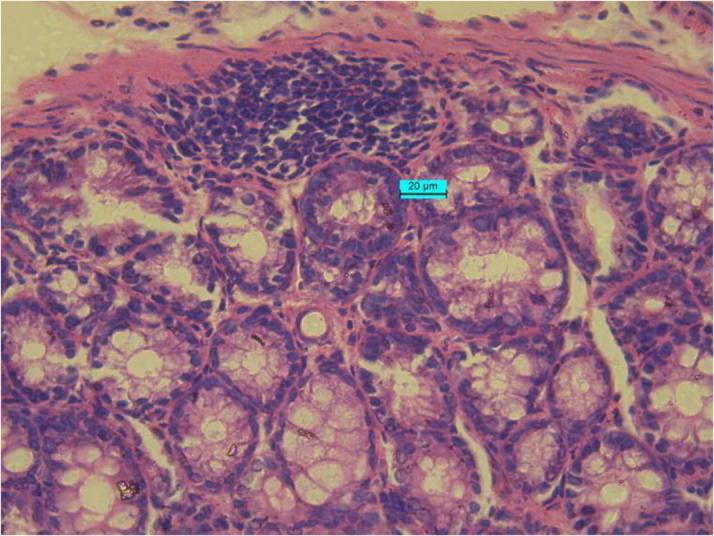

Intestinal cancer is a disease with high morbidity and high mortality in China. Previous studies have shown that Codonopsis foetens can inhibit cellular autophagy and promote the apoptosis of intestine cancer cells. Based on metabolomics method coupled with liquid chromatography-mass spectrometry (LC-MS) technology, we aimed to analyze intestinal small molecule metabolites in the intestinal cancer model group and the Codonopsis foetens treated group. Principal component analysis (PCA) and Partial Least Squares (PLS-DA) were used to identify the pattern of the data. And the metabolic characteristics of the cancer model group were explored based on the metabolic differences between the groups. Multivariate statistical analysis revealed that metabolites presented with differences included: Acetamide, Phosphoric acid, Hydrogen sulfite, Pyruvic acid, Cytosine, 2-Hydroxypyridine, Phosphoric acid, Uracil, Gamma-Aminobutyric acid, Glycerol alpha-monochlorohydrin, Thiosulfic acid, L-Valine, Cysteamine, Taurine, Creatine, Homocysteine, Hypoxanthine, Se-Methylselenocysteine, 5-Hydroxymethyluracil, Oxoglutaric acid, LysoPC(20:0), LysoPC(22:4(7Z,10Z,13Z,16Z)), LysoPC(18:2(9Z,12Z)), LysoPC(16:1(9Z)), LysoPE(0:0/16:0), LysoPE(0:0/18:2(9Z,12Z)), LysoPE(18:0/0:0), LysoPE(20:1(11Z)/0:0), etc. Combined with metabolic pathway analysis, pathways presented with differences included: Citrate cycle (TCA cycle), ABC transporters, 2-Oxocarboxylic acid metabolism, Taurine and hypotaurine metabolism, Butanoate metabolism), Phenylalanine, tyrosine and tryptophan biosynthesis, Biosynthesis of amino acids, Protein digestion and absorption, Aminoacyl-tRNA biosynthesis, C5-Branched dibasic acid metabolism, GABAergic synapse, Proximal tubule bicarbonate reclamation, Mineral absorption, Phenylalanine metabolism. The results showed that the proliferation of intestinal cancer cells caused cell metabolism disorders, manifesting as changes in metabolic pathways and resulting in changes in metabolites.